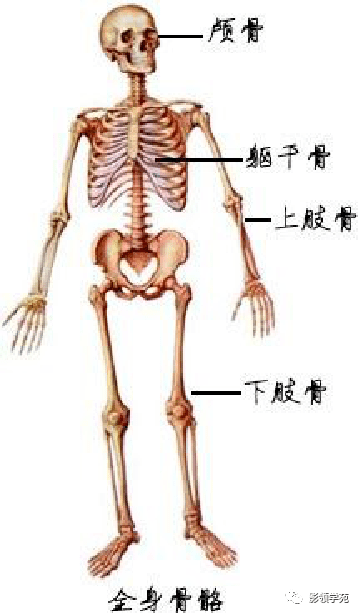

骨骼系统

骨骼系统